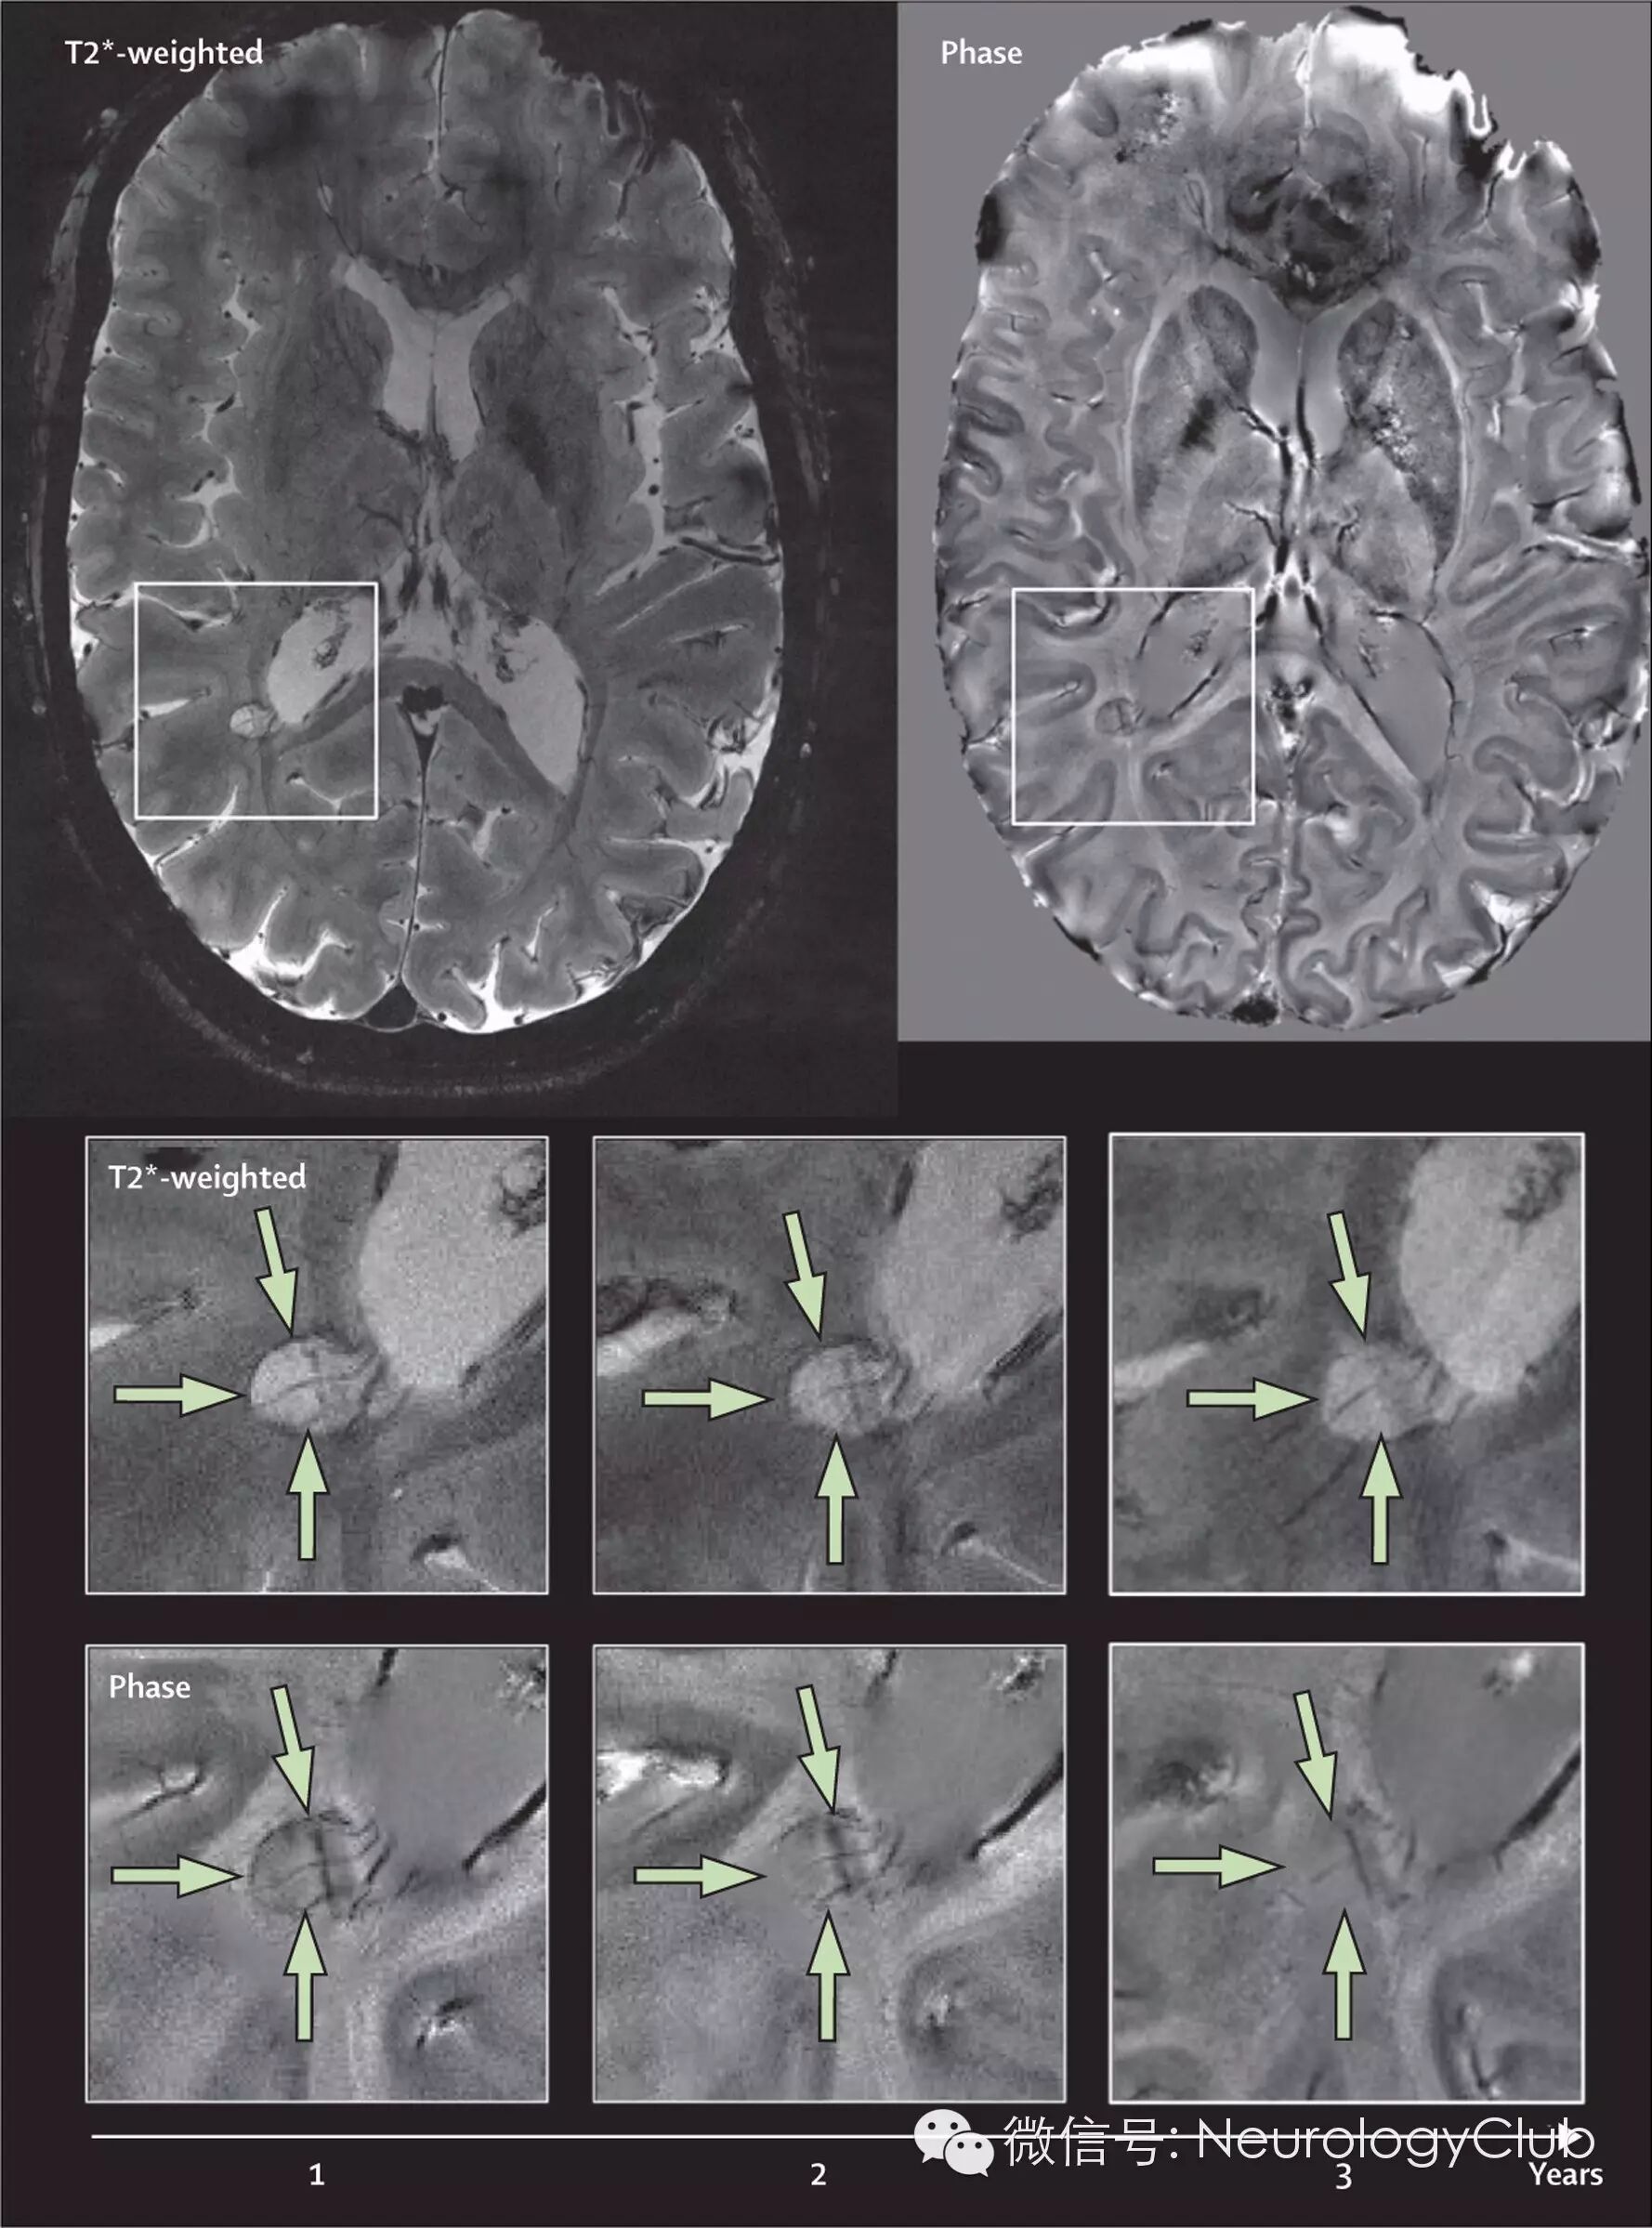

图3  一位复发-缓解型MS患者超高场强颅脑MRI表现

[一位36岁女性复发-缓解型MS患者的7.0T MRI上梯度回波和相位序列的水平位T2像。图中可见脑室周围不强化病灶伴顺磁性环(绿色箭头)。所有的图均可见一条明显的中央静脉。该病灶在3年随访时形态基本保持不变(放大框)]